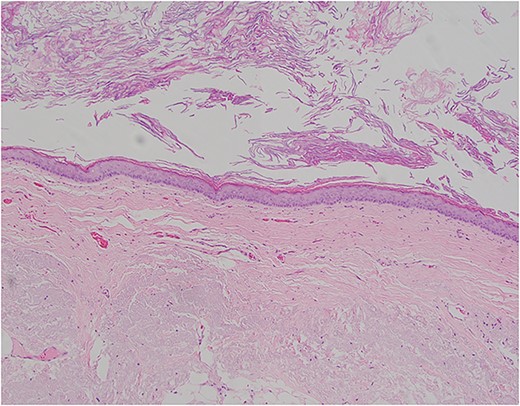

Pictomicrograph of an H&E-stained section of the cyst taken at 10× magnification. No solid areas were identified in the cyst, and no other tissue types were identified besides squamous epithelial lining within a thin wall of loose connective tissue. No cartilage, bone, or glandular tissues were identified. No immature or embryonic-type tissues were identified.